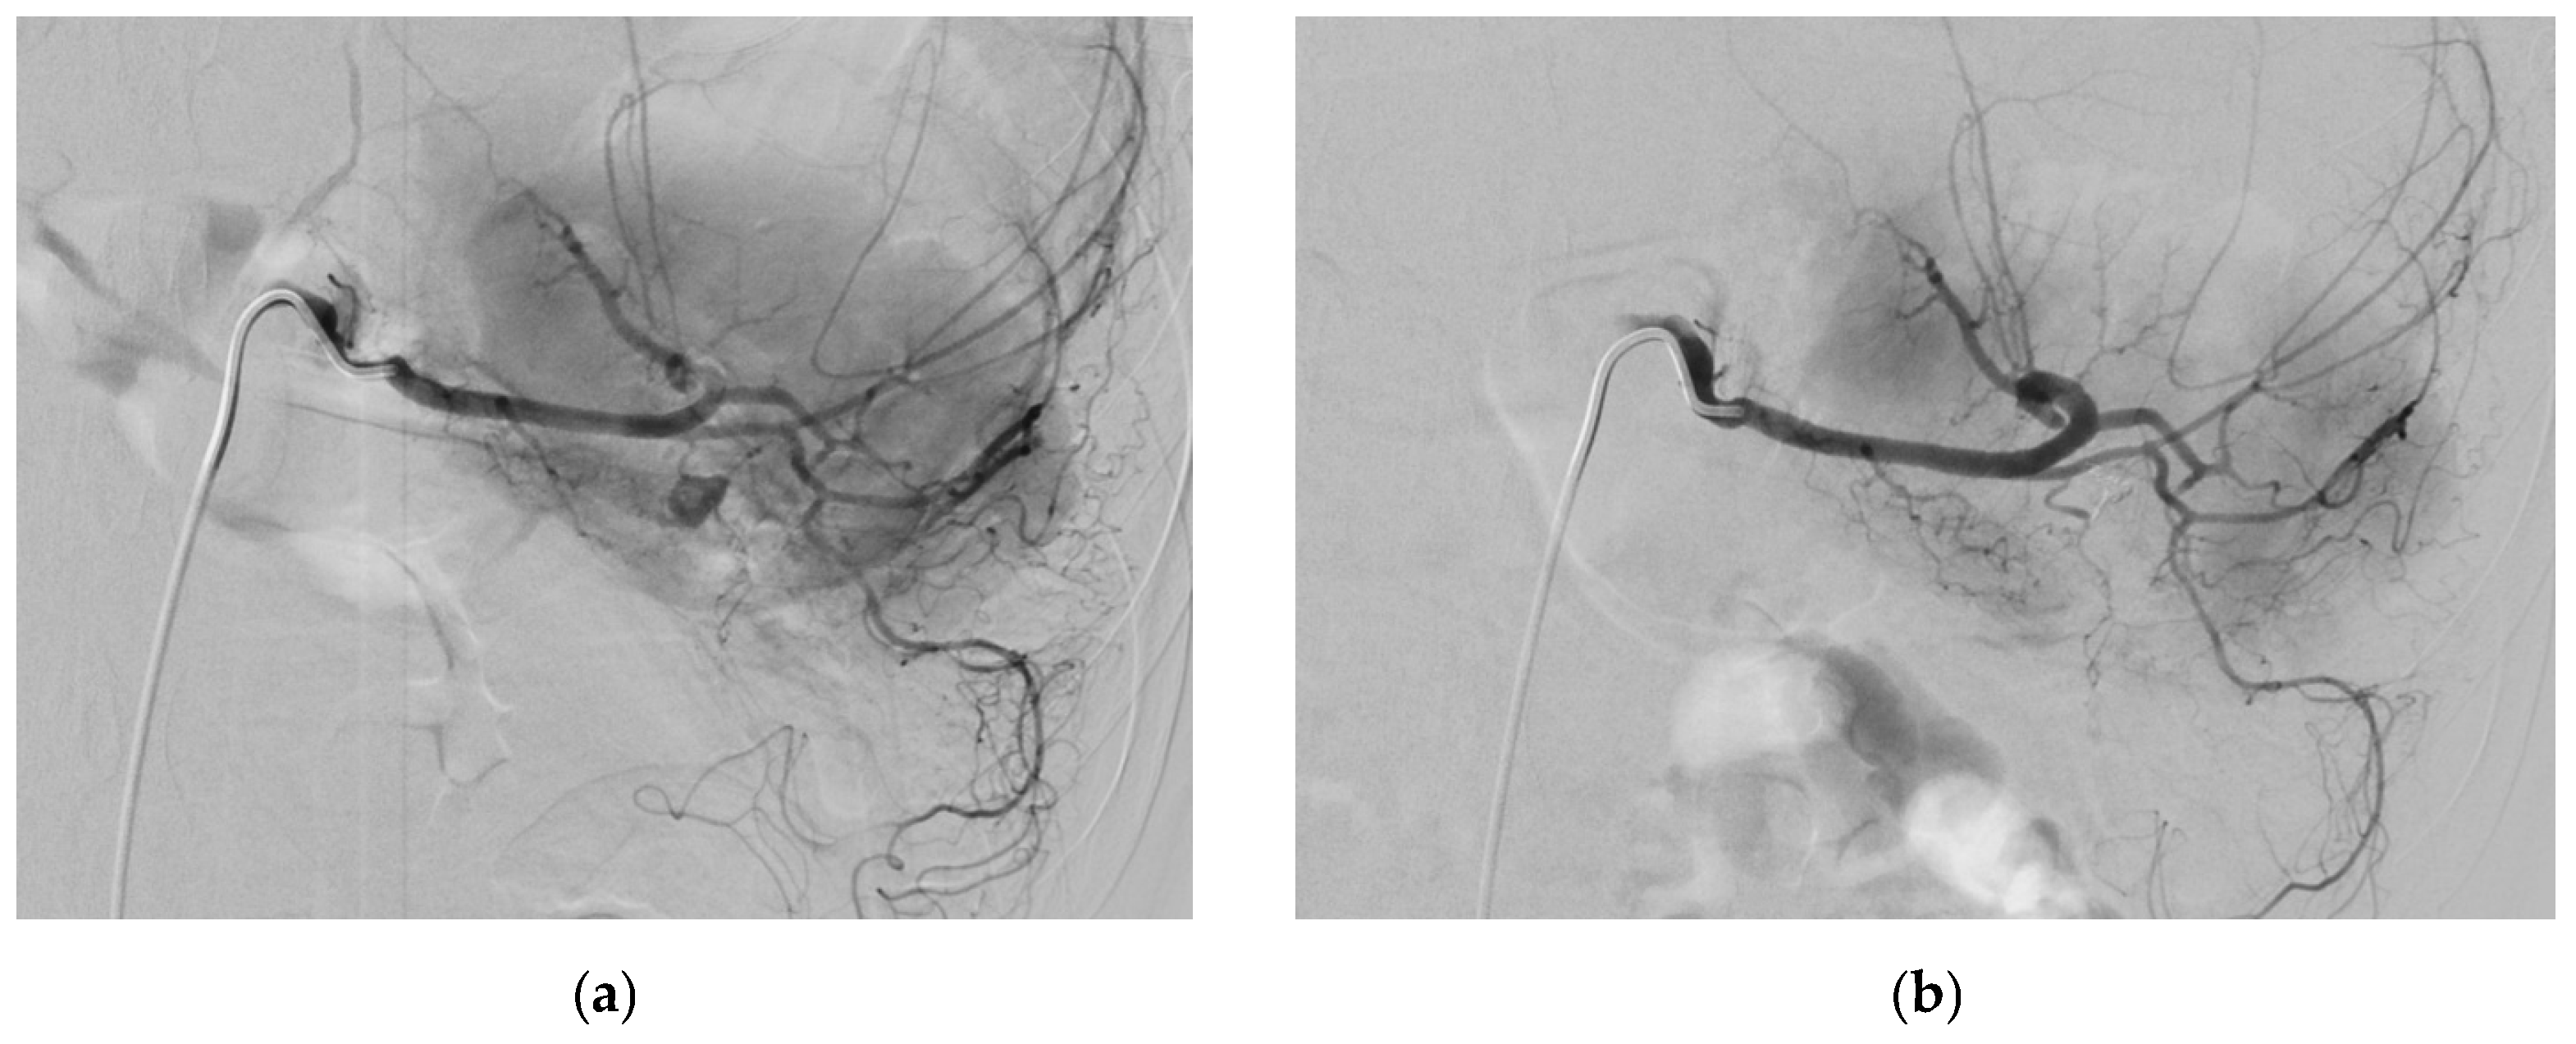

3.1. Superior Mesenteric Artery

3.1.4. Diagnosis

3.1.5. Management